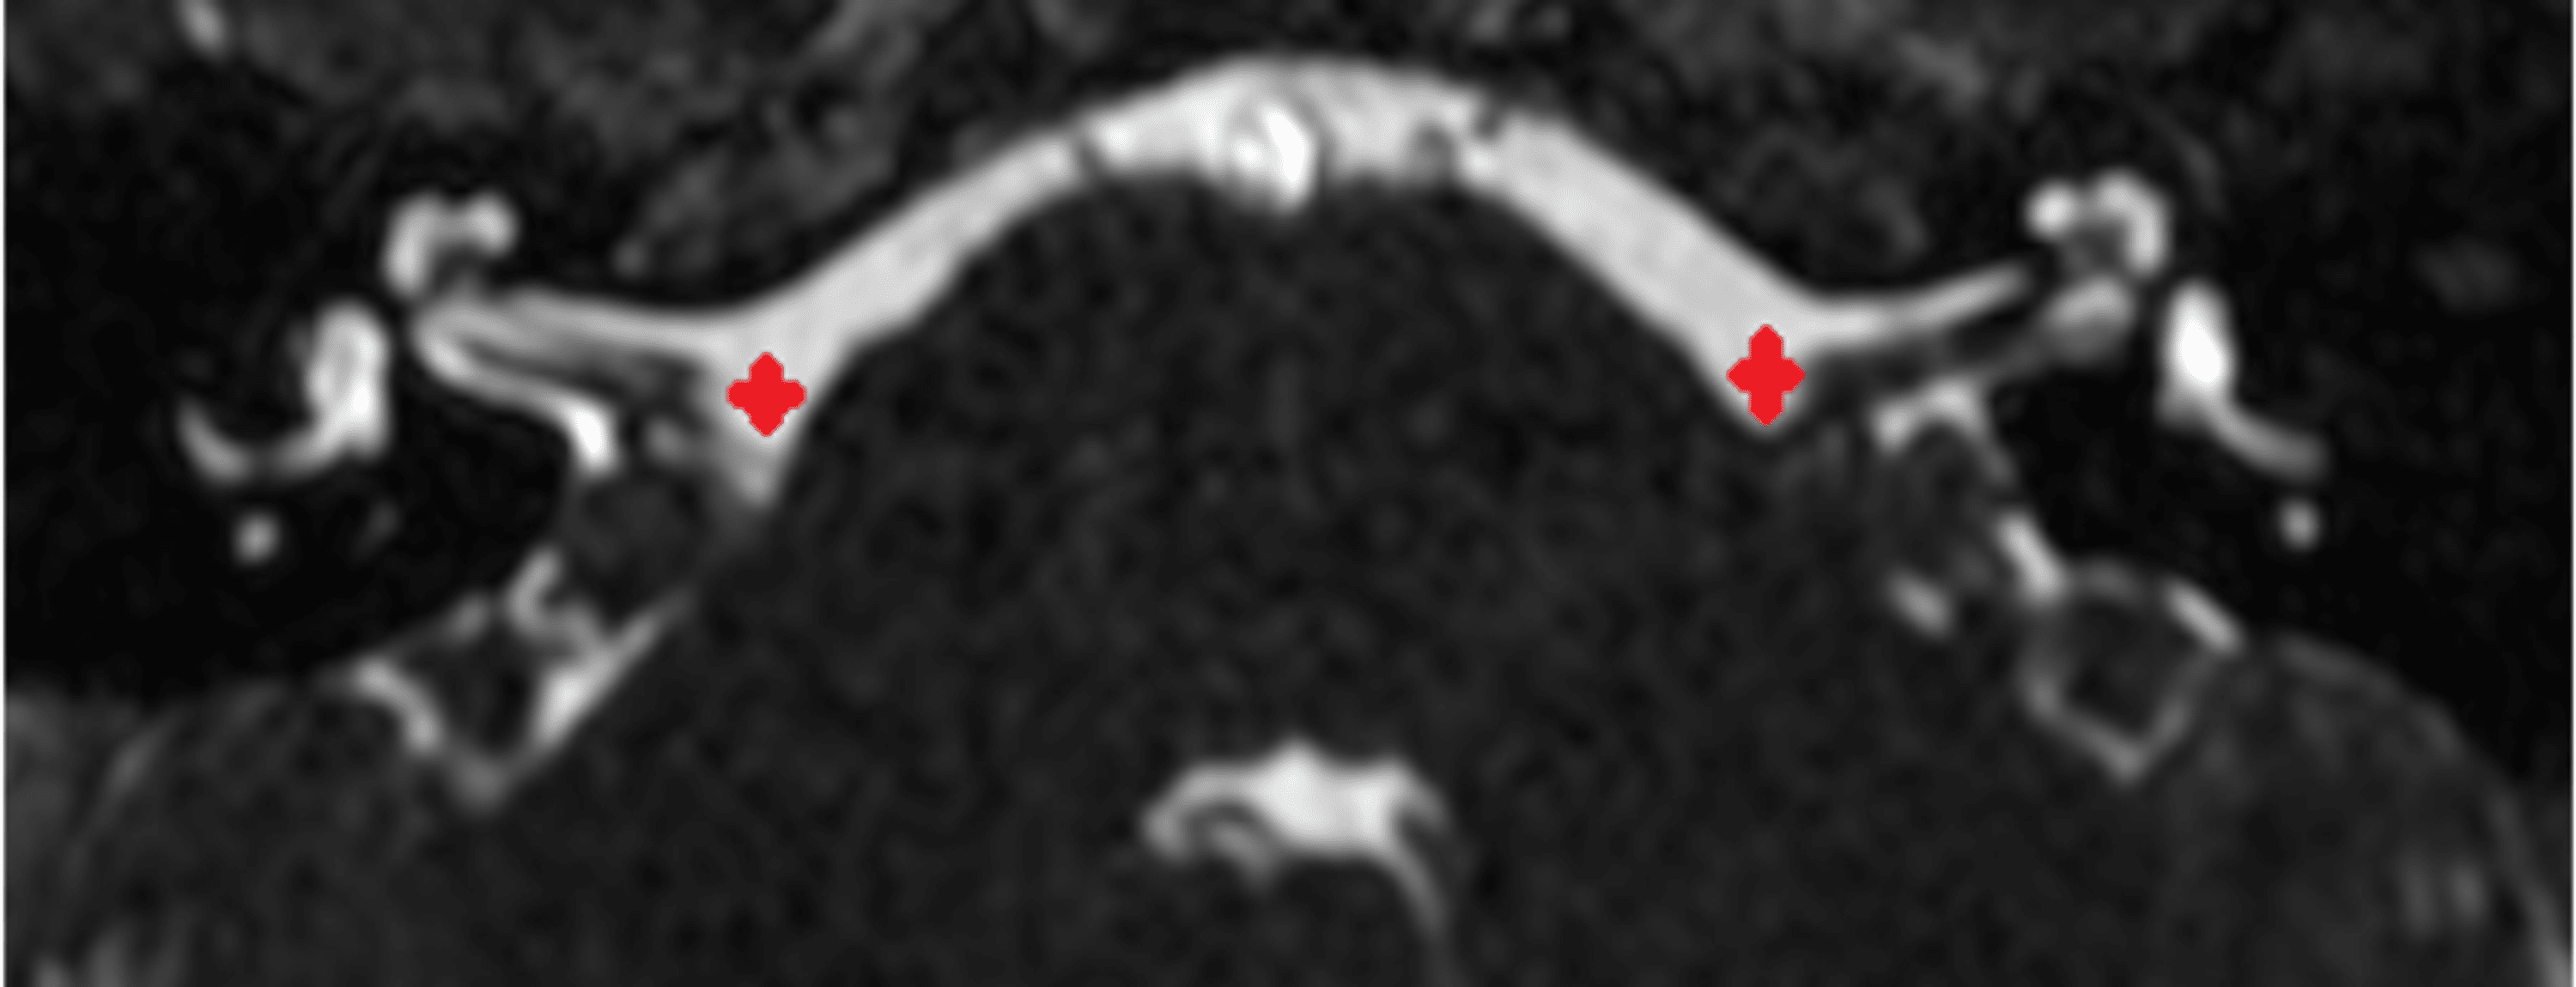

From radiopaedia.org

Ascending auditory pathway (annotated MRI) Image Hearing Damage From Mri overall, it seems that mri scanner noise does not pose a significant risk for permanent hearing loss as long as. Other clinical symptoms appear to increase the diagnostic yield of mri, such as the presence of unilateral vs bilateral tinnitus and vertigo/dizziness, which was confirmed in our study. hearing damage after exposure to mri noise depends on the. Hearing Damage From Mri.